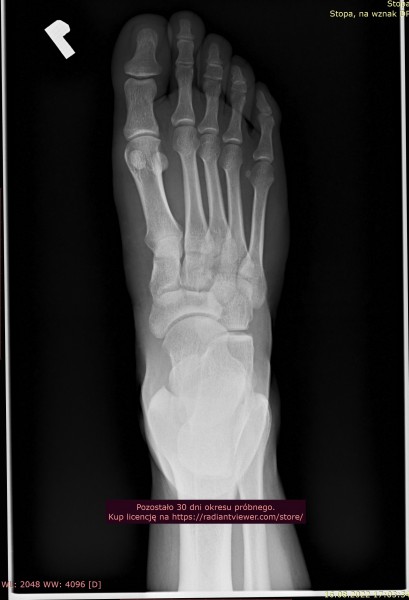

Rok temu poszedłem do ortopedy z bolem piety. Nie robil zadnych zdj RTG czy usg tylko wyslal na rehabilitacje bo wydawało mu się, ze to ostroga piętowa. Po rehabilitacji bol minal dopiero po ok 2 msc a, ze byla zima to i mobilnosc mniejsza mniej sportu wiec bol ustal. Na wiosne zaczalem jezdzic na rowerze plus granie w pilke na orliku. Bylo ok az do ubieglego tygodnia. Bol piety powrocil. Zrobilem prywatnie rtg, jednak opis bede mial dopiero za tydzien. Czy na zalaczonym zdjeciu widac ostroge lub cos innego niepokojacego przez co moze mnie boleć ?